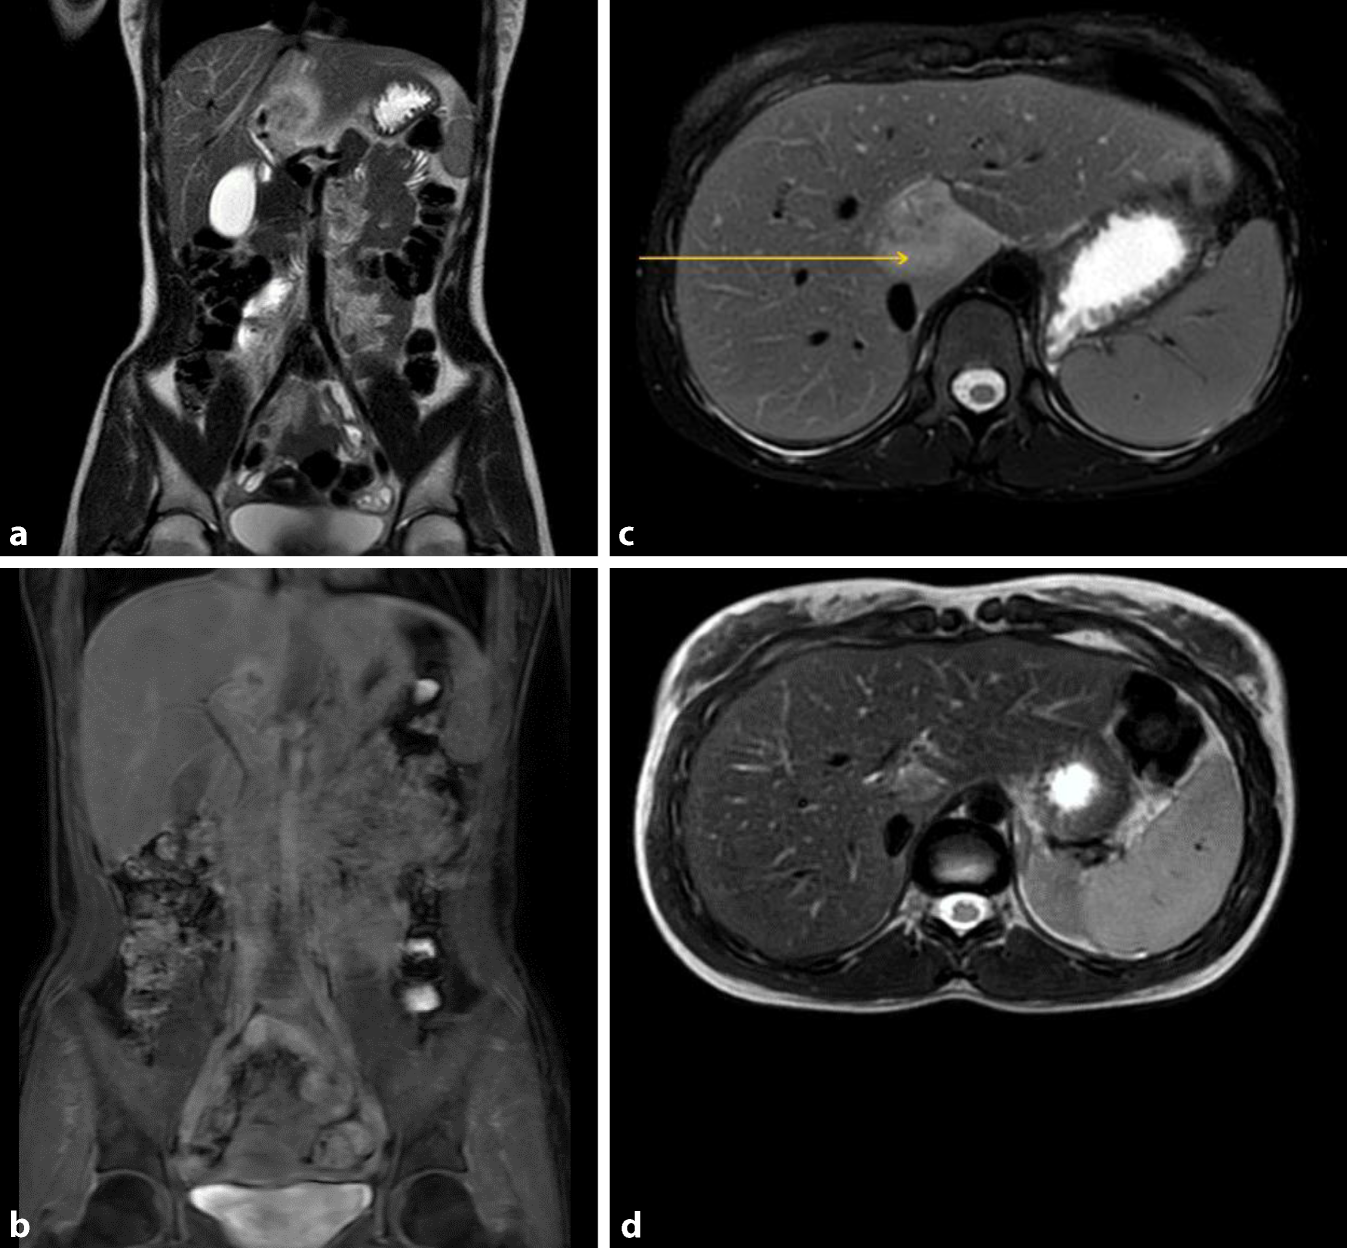

Bildgebende Untersuchung (MRT; Abb. 1)

Hier zeigte sich initial eine hyperperfundierte Raumforderung (ca. 2,5 × 2 0,0 × 3,4 cm) im Lebersegment I mit zentralem Wash-out. Eine etwas kleinere ebenfalls hyperperfundierte Läsion mit zentralem Wash-out war auch in Segment VI zu sehen. Es bestand bildmorphologisch kein Anhalt auf eine Kolitis, nebenbefundlich zeigten sich am ehesten zyklusbedingt zystische Ovarien beidseits.

Abb. 1

a Vor Therapie – MRT T2 TSE SSH koronar. b Nach Therapie – MRT cs mDIXON koronar. c Vor Therapie – MRT T2 SPIR. d Nach Therapie – MRT T2 TSE. Pfeil suspekte Leberraumforderung

Die vorgestellte Patientin wurde zunächst empirisch antibiotisch mit Piperazillin/Tazobaktam anbehandelt. Bei stetig fallenden Infektparametern konnte die Antibiose zeitgerecht entfernt werden. Hiernach zeigten sich eine Normalisierung der Infektwerte und ein regredienter Residualbefund in der MRT. Die Patientin berichtete hierzu passend über eine Besserung der abdominellen Schmerzen. Der Residualbefund soll in regelmäßigen Verlaufsuntersuchungen mittels Schnittbildgebung kontrolliert werden. Bei der jungen Patientin wurde als Modalität die MRT gewählt und aktuell ein 3‑monatiges Intervall festgelegt.